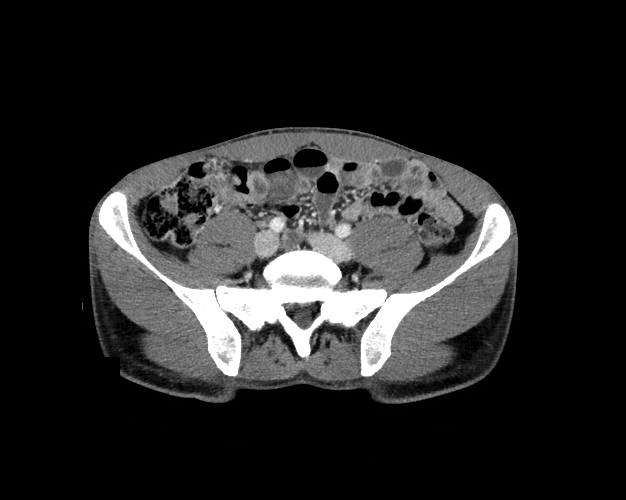

Body

Covers abdominal CT anatomy.